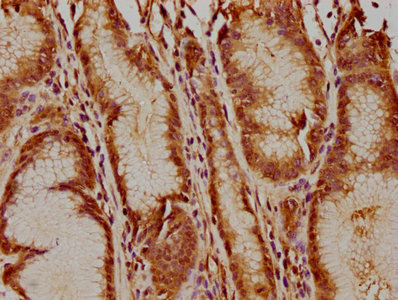

IHC image of CSB-PA427555LA01HU diluted at 1:400 and staining in paraffin-embedded human gastric cancer performed on a Leica BondTM system. After dewaxing and hydration, antigen retrieval was mediated by high pressure in a citrate buffer (pH 6.0). Section was blocked with 10% normal goat serum 30min at RT. Then primary antibody (1% BSA) was incubated at 4°C overnight. The primary is detected by a biotinylated secondary antibody and visualized using an HRP conjugated SP system.